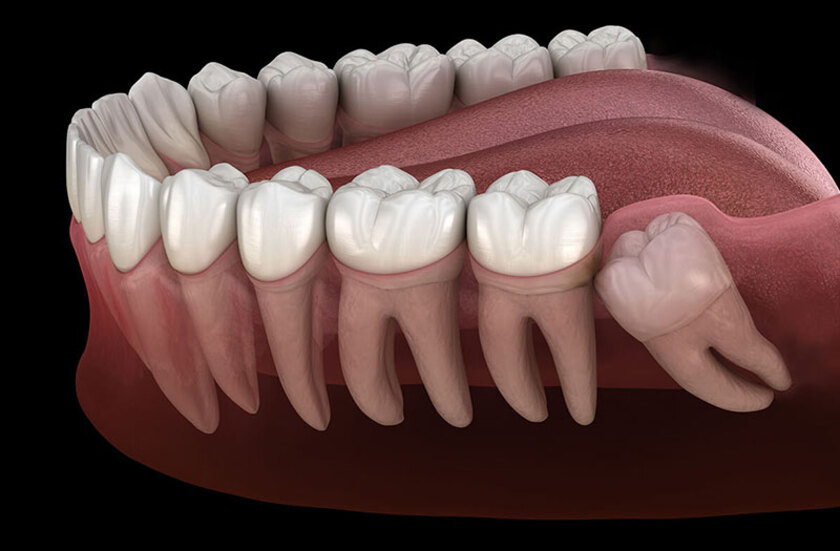

Mọc răng khôn

Đây là tình trạng khá phổ biến ở lứa tuổi trưởng thành khi răng khôn mọc ngầm, mọc lệch gây đau nhức và ảnh hưởng đến các răng bên cạnh. Răng khôn hay răng số 8 là chiếc răng cuối cùng mọc trên cung hàm. Do không đủ chỗ trong cung hàm cho những chiếc răng này mọc nên chúng thường mọc ngầm hoặc không đúng vị trí. Chúng gây ra tình trạng đau âm ỉ kéo dài và lặp đi lặp lại nhiều lần. Răng khôn mọc còn khiến nướu bị sưng tấy, ăn uống khó khăn. Đôi khi còn gây sốt, chán ăn, ảnh hưởng nghiêm trọng đến sinh hoạt hàng ngày.

Cách trị đau răng do mọc răng khôn

Bệnh nhân nên được chụp phim để biết răng khôn mọc thẳng hay lệch. Bác sĩ có thể kê đơn thuốc giảm đau và thuốc kháng sinh để giảm viêm mô mềm và ngăn ngừa tổn thương nghiêm trọng cho các răng khác. Trường hợp răng mọc ngầm, mọc lệch cần được nhổ bỏ để tránh đau nhức và ảnh hưởng đến các răng khác.

Nhổ răng khôn mọc lệch giúp tránh đau nhức và ảnh hưởng đến các răng khác